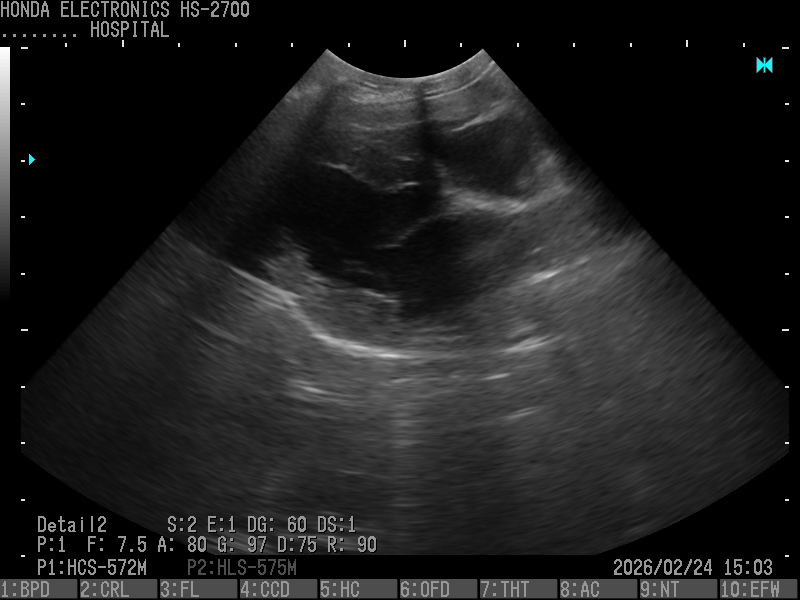

3.腎臓(パピヨン・10歳)

プローブ:HCS-572M

H-res:Detail2